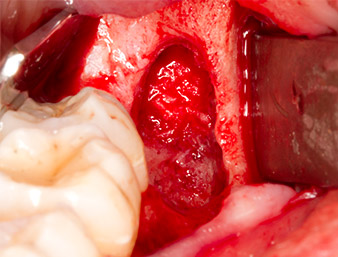

Wurzelrest 38

Abb. 7: Der Wurzelrest 38 ist in seiner Alveole gut dargestellt für die nachfolgende Entfernung.